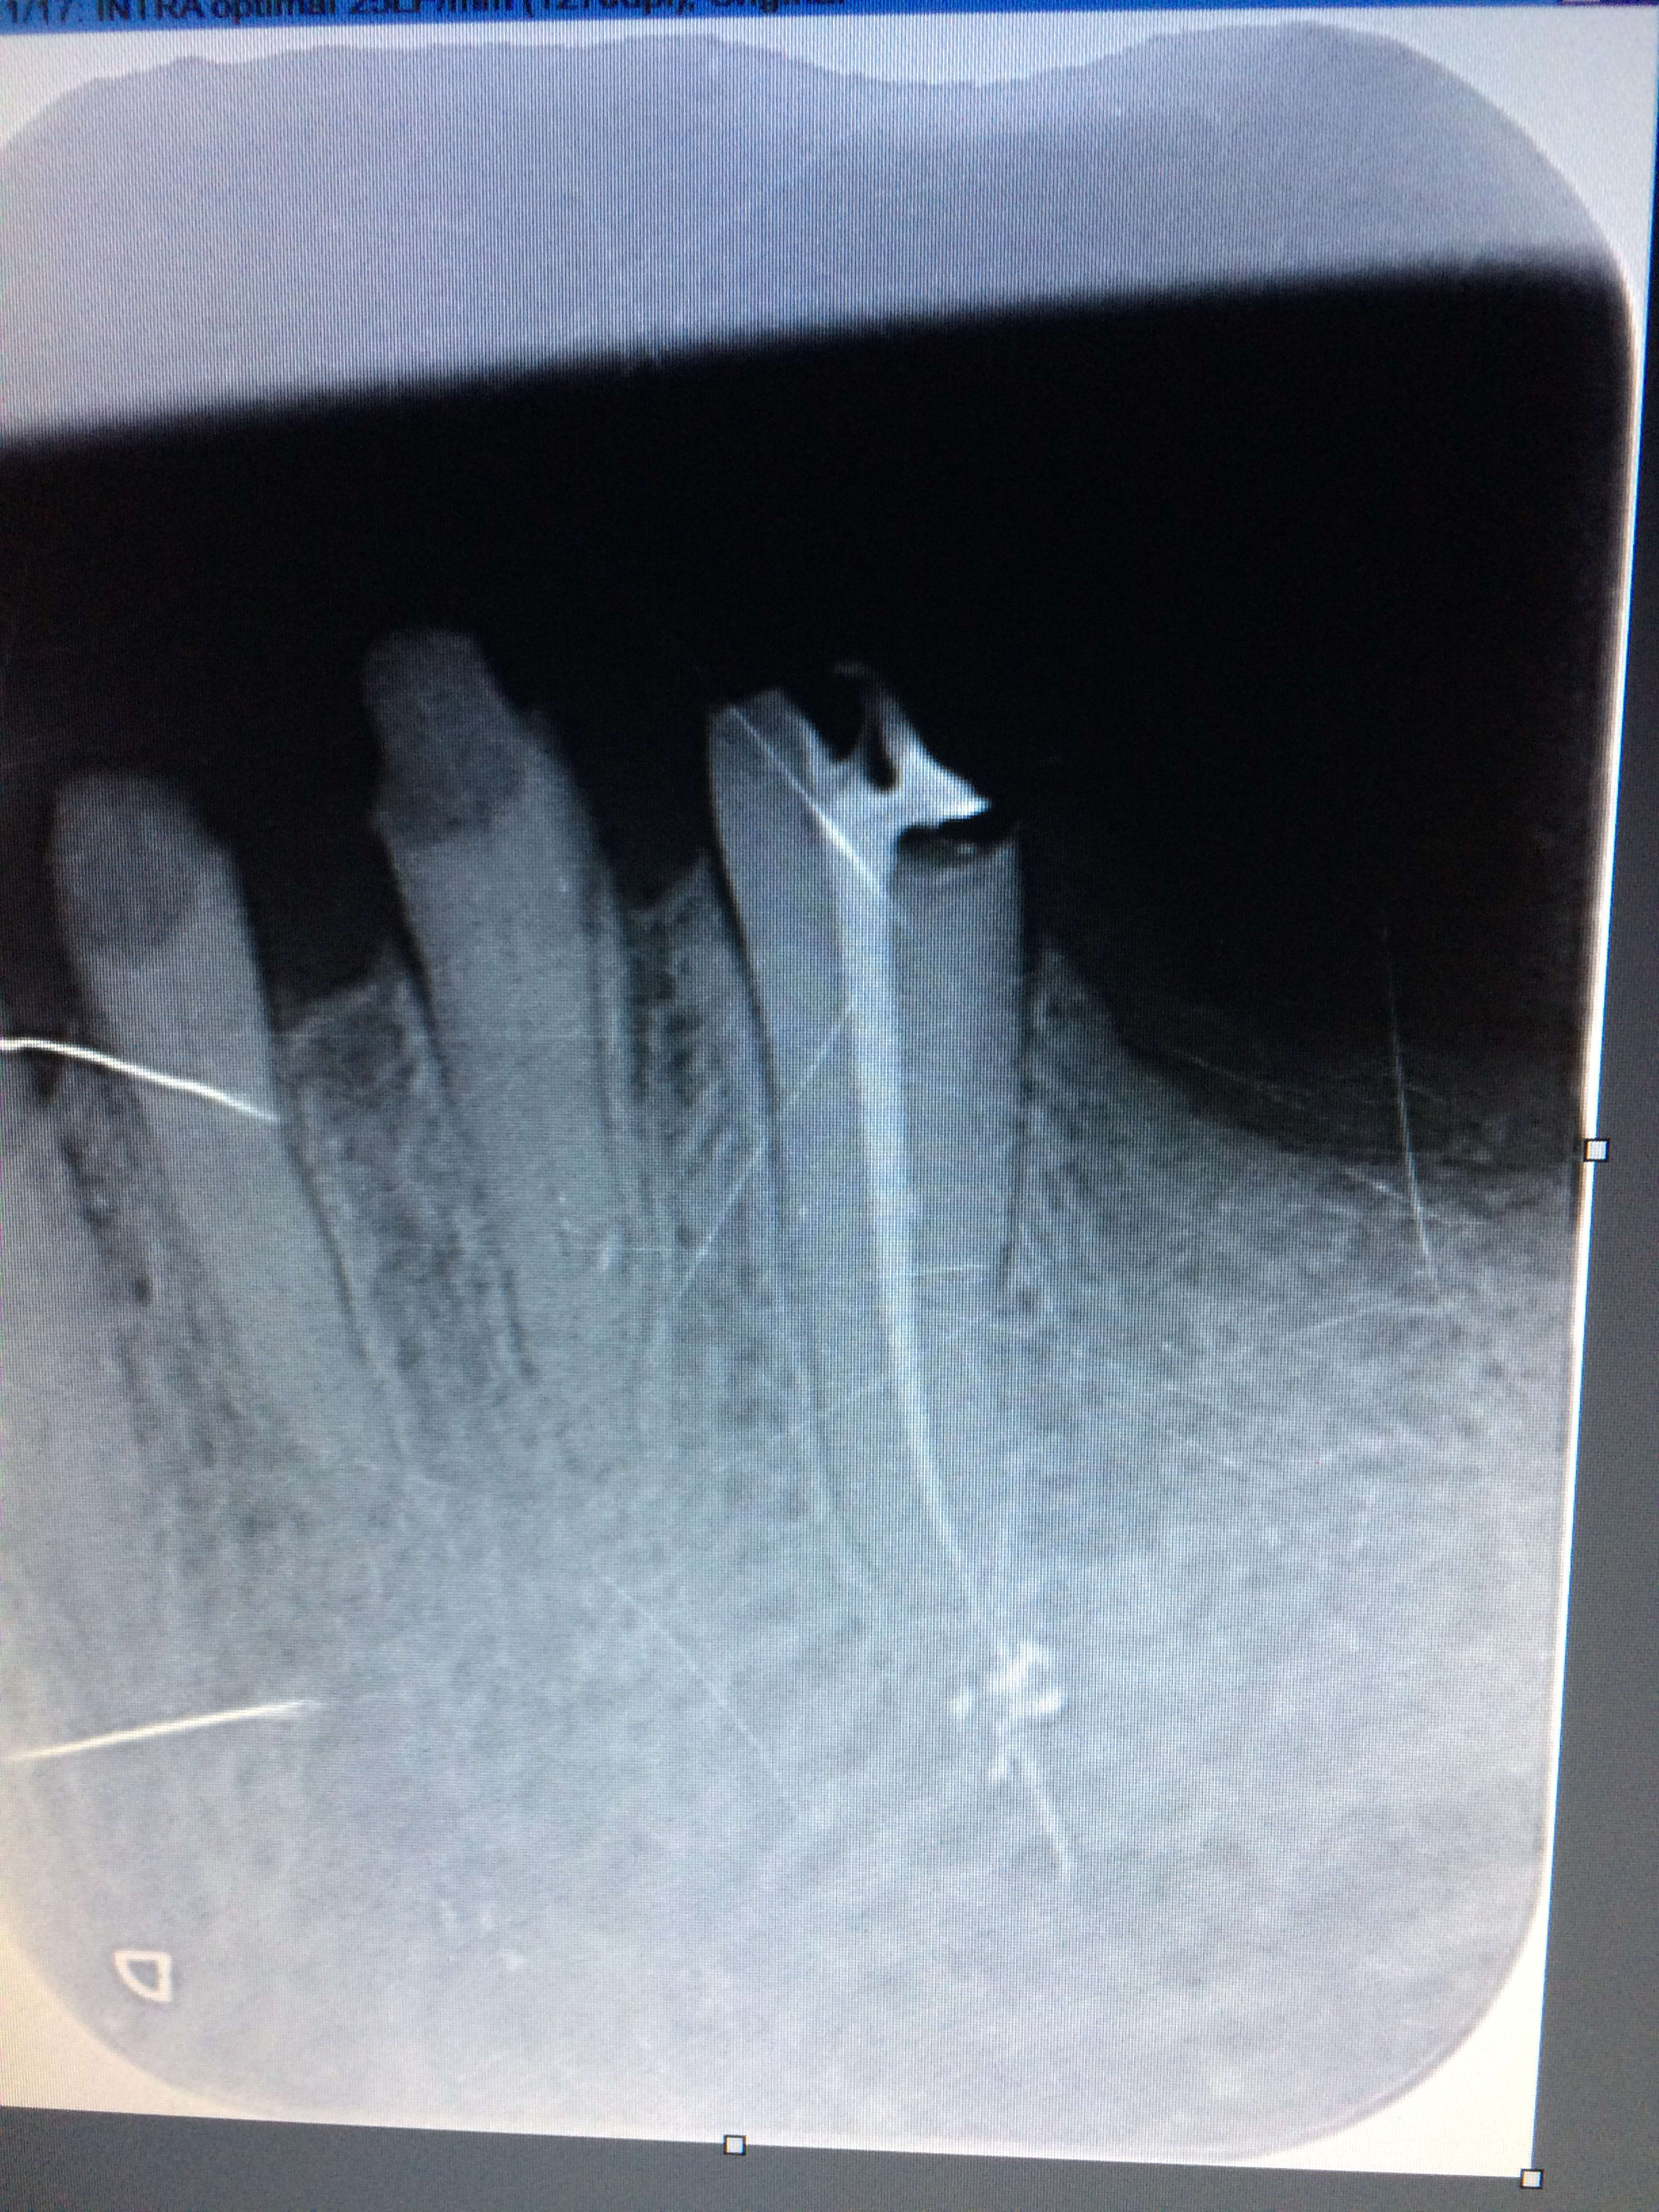

Je ne fais qu'une radio préop avec lime et une postop, je n'ai pas de radio perop.

tu penses que j'ai surtravaillé le canal..? mais poutant j'étais à la bonne longueur d'après la radio cathé et je n'ai eu aucun saignement..

>Je ne fais qu'une radio préop avec lime<

heuh, ca veut dire peroperatoire, non? :-) Bah, mets la nous en visu!

La voilà ! :)

Img 4454 ampdry - Eugenol

Tu jauges ton diamètre apical avec quoi?

Le trait blanc tu es sûr que ce n'est pas ton capteur?

Pour moi, ça manque de conicité apicale, donc le ciment ou la gutta peut plus facilement dépasser par la pression exercée : pas de cône d'arrêt.